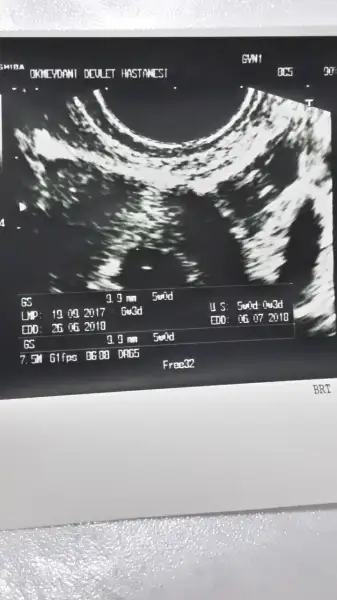

Eki Görüntüle 2065309 Eki Görüntüle 2065309 Eki Görüntüle 2065309 kizlar ben gecen hafta cuma gunu 5+3 iken gitmistim. Ilk gebeligim oldugu icin yorumlayabilir misiniz? Devlet hastanesine gittim doktor pek bi sey soylemedi. 1 hafta sonra tekrar gel dedi. Ama yarina randevu alamadigim icin haftaya pazartesi gidecegim. O zmn sat'a gore 6+6 olmus olacagim

Kese olusmus. Bebek olusumu yeni baslamis dedi ama bana cok karisik geldi bu forograf. O yuzden bilen birisi varsa diye sormustum. Cevabiniz icin tesekkur ederimCanım vlla bişey anlayamıyorum ben. Doktor kese var vs demedi mi?